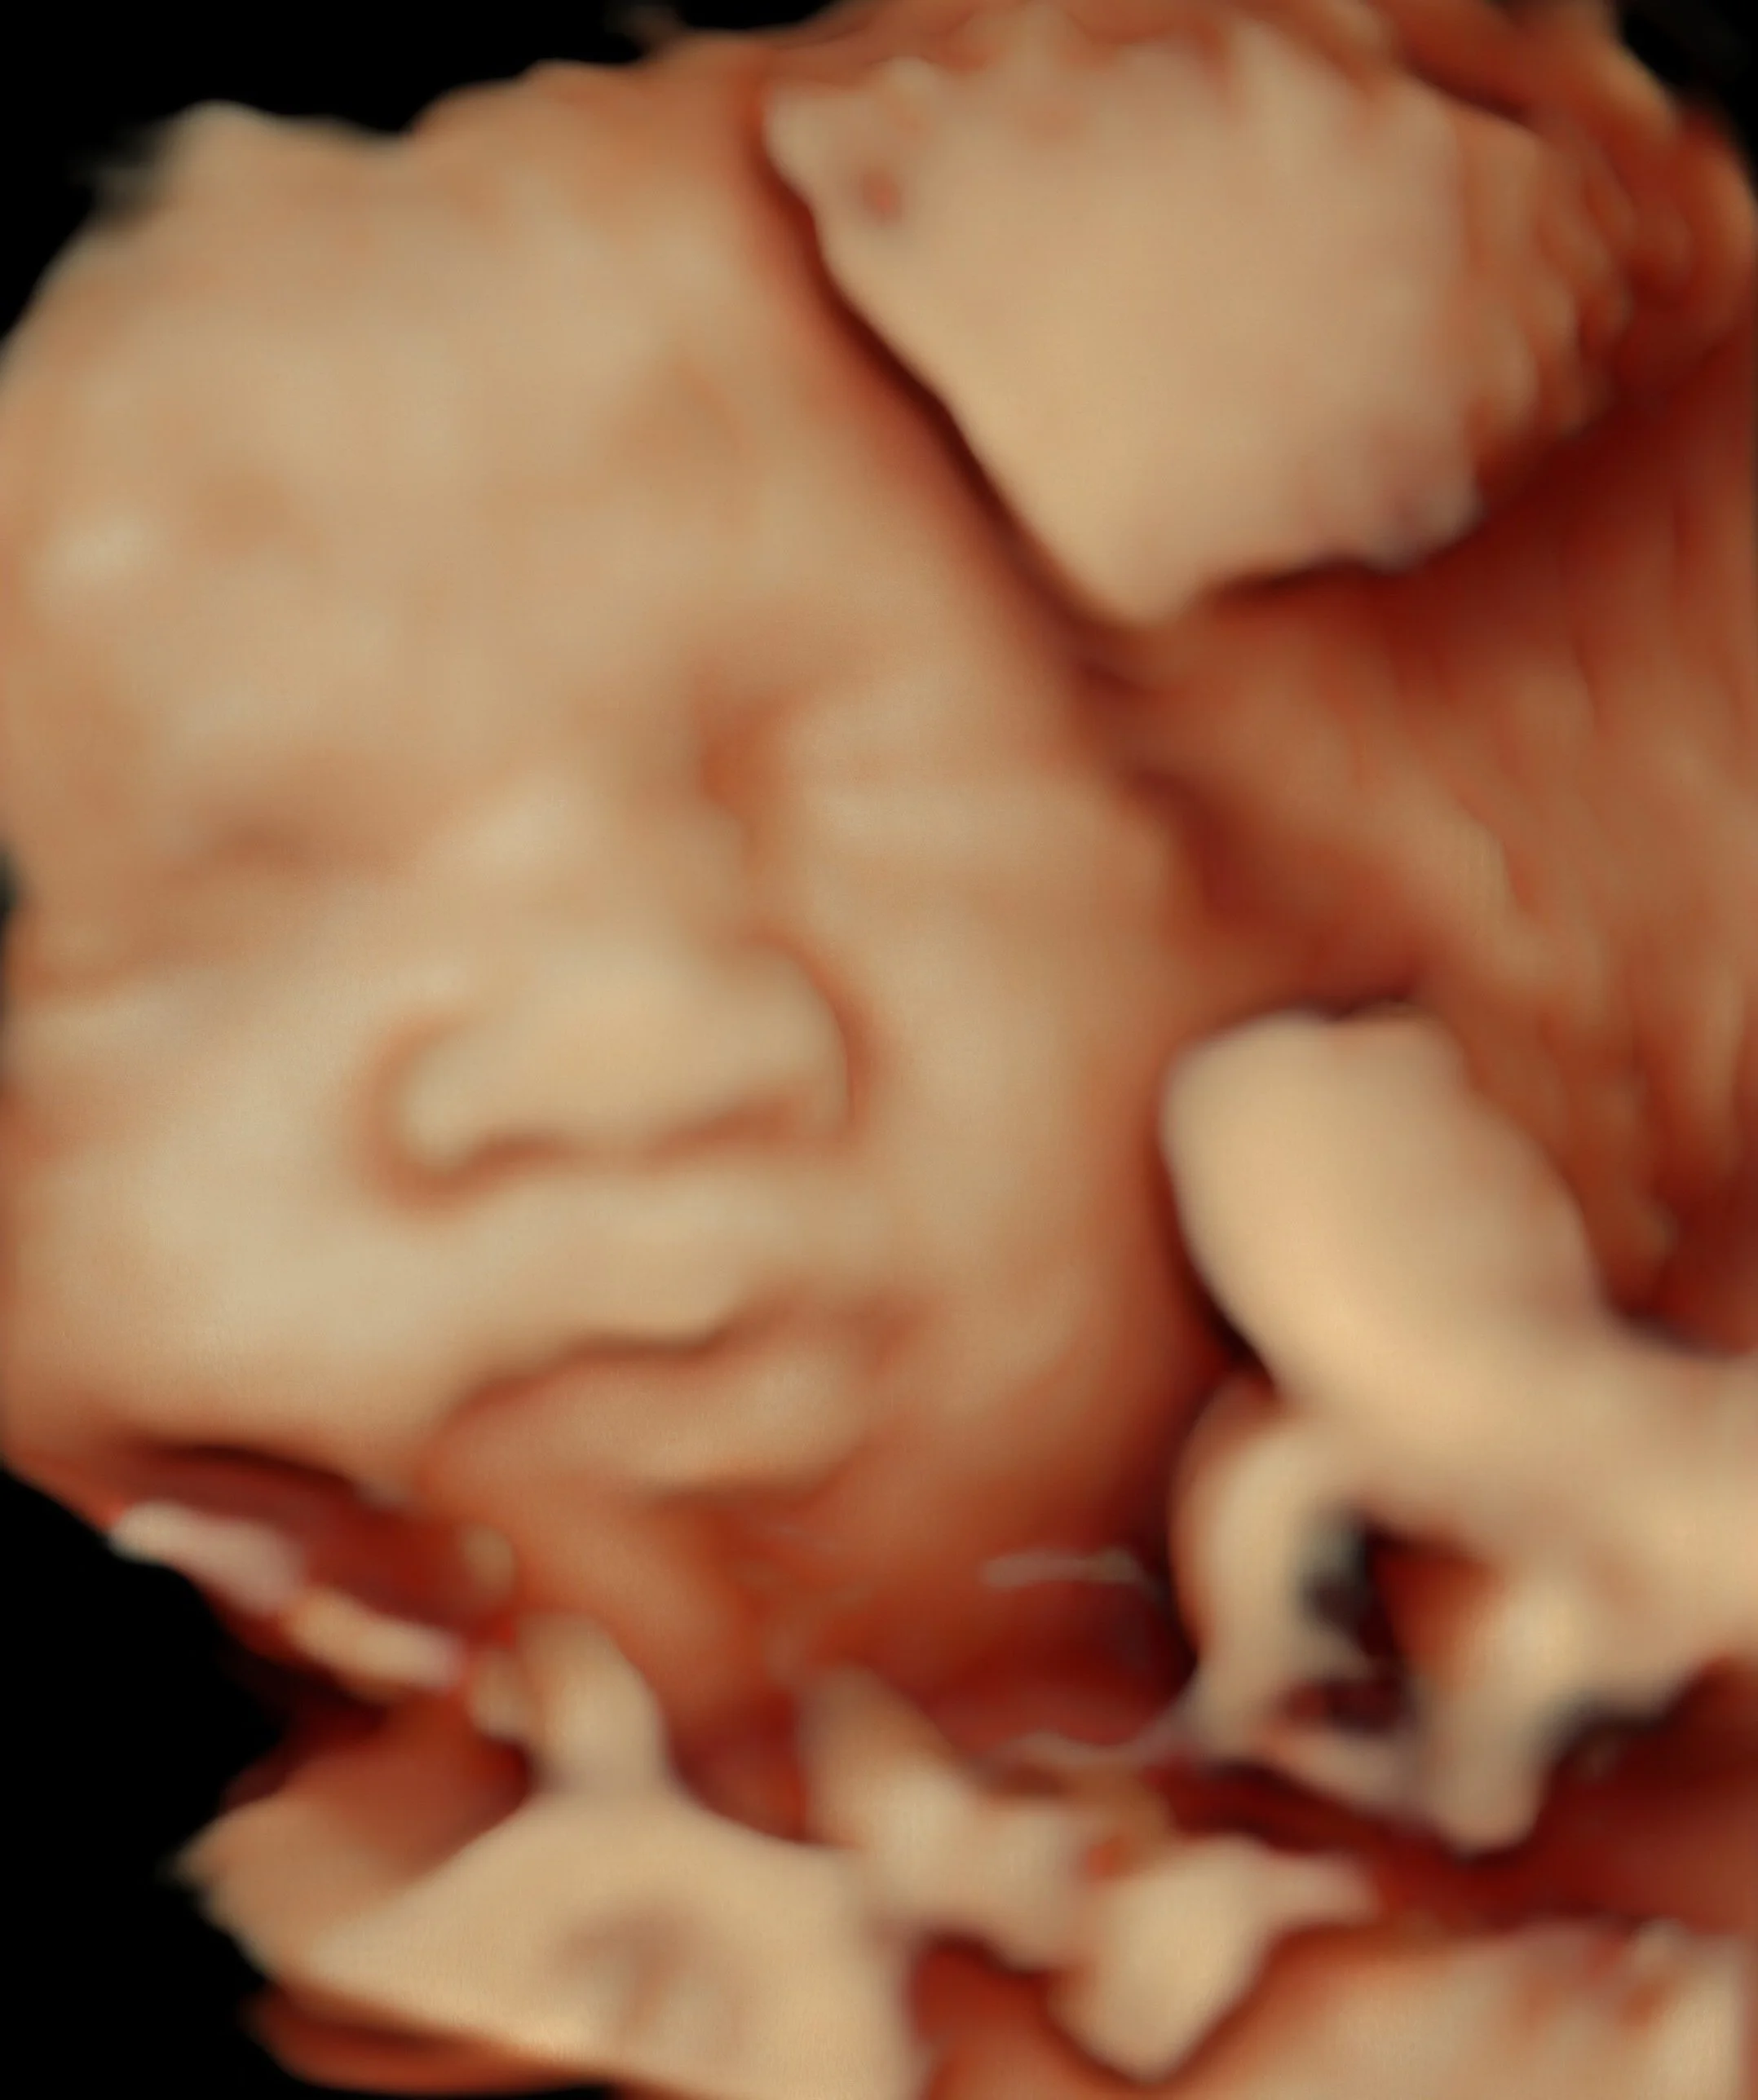

Weeks 23 to 33

3D/4D Up Close -- HD Live

See your baby's face, expressions, hands, and real-time movements in stunning 3D/4D/HD detail on our projection screen.

Best window for 3D/4D -- sweet spot is weeks 26 to 30

3D/4D Baby Ultrasound Tampa, FL -- HD Live Sessions (Best Weeks 23 to 33)

See your baby's face, hands, and real-time movements in breathtaking 3D/4D/5D/HD detail on our large projection screen with LED ceiling. Available at any stage of pregnancy -- best results between weeks 23 and 33. The sweet spot is weeks 26 to 30 when baby has developed facial features and still has plenty of space to move. No referral needed. Se habla espanol. From $139.

See your baby's face, hands, and real-time movements in breathtaking 3D/4D/5D/HD detail on our large 65" screen with LED ceiling. Available at any stage of pregnancy — best results between weeks 23 and 33. The sweet spot is weeks 26 to 30. No referral needed. Se habla español. From $139.